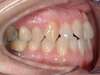

Cas 4 : Description

Chevauchement sévère. Traitement multibague sans extraction.

Avant

Après